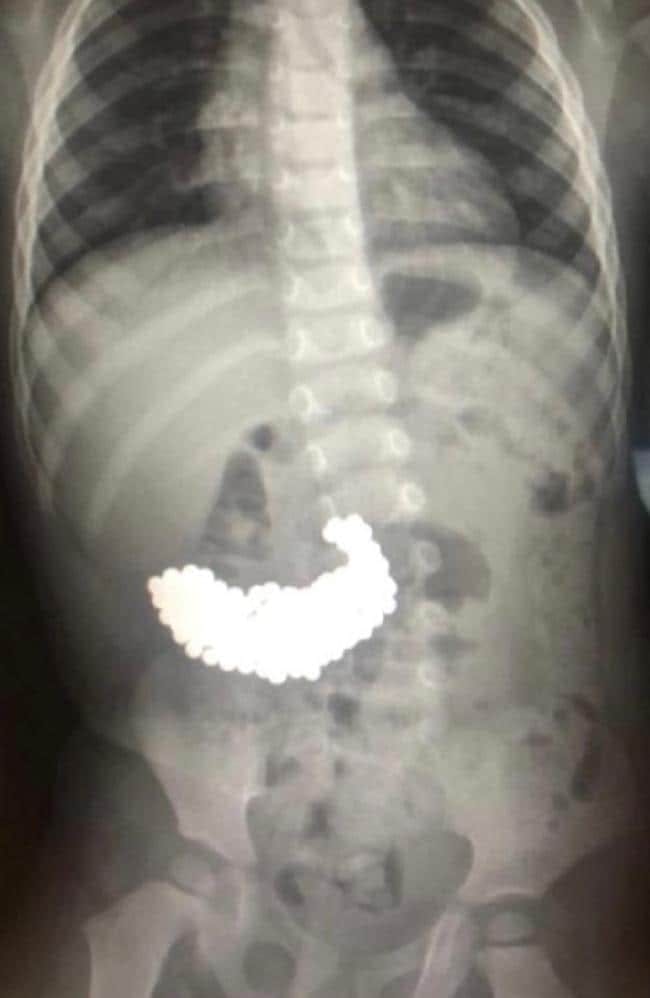

Chokerede læger i Rusland fik sig noget af en overraskelse, da de tog et røntgenbillede af en toårig drengs mave.

I mavesækken fandt de nemlig hundredvis af magnetiske kugler, som den lille gut havde slugt måneder forinden.

Kirurger fjernede nænsomt de 209 ”potentielt dødelige” metalkugler én efter én.

Under den to timer lange operation opdagede de, at nogle af kuglerne havde fået skarpe kanter, hvilket kunne have resulteret i, at de havde skåret sig vej igennem mavesækken.